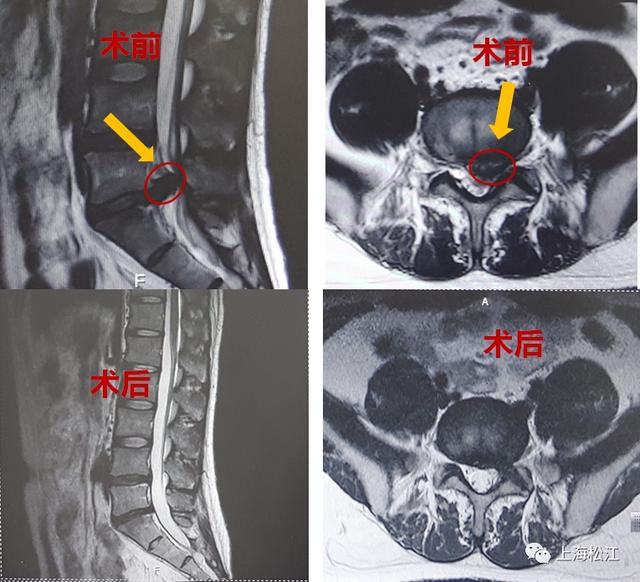

大学毕业后,小吴成为了一名软件工程师,也就是人们常说的程序员。常年久坐在电脑前,小吴体型越来越胖,腰越来越疼,腿部也开始出现疼痛的症状。经医院诊断,小吴腰5骶1腰椎间盘突出,压迫神经根伴有局部钙化。这对年纪轻轻、事业刚刚起步的小吴来说无疑是巨大打击。“不要说上班,我连基本生活起居都有困难。”小吴坦言。

四处就诊无果后,对微创手术将信将疑的小吴来到了上海市第一人民医院脊柱外科“碰碰运气”。而这一来,真让小吴“碰着了”。经胡硕副主任医师初步评估,小吴可以通过保留椎间盘的微创手术方案治疗腰椎间盘突出。“他椎间盘突出部分确实比较严重,突出部分压迫了一侧神经根,并伴有钙化,但是未突出部分退变不严重。微创手术后,配合包括减重、改善坐姿、腰背肌肉锻炼等综合治疗方案,还是可能达到理想的治疗效果。”

不久之后,小吴进行了局麻下的椎间镜手术,术后小吴的腿痛症状消失了,第二天,小吴就顺利出院了。出院后,小吴积极改善生活方式,减重20多斤,平时工作中也注意调整坐姿、锻炼腰背肌,经过长达2年多的随访观察,未出现腰椎间盘突出复发的情况。